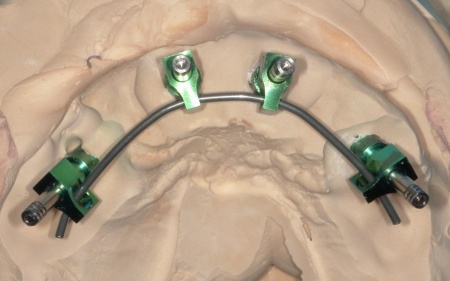

①上の歯7本、右下の奥歯2本を抜歯する。上あごには抜歯と同時に4本のインプラントを埋め、その上に10本分の仮歯を取り付けるオールオンフォーを行う。

インプラントの種類には、あごの骨と結合する力に優れたオステム社のETⅢを採用。インプラントが骨にしっかり定着するまでの間は、通常のインプラントよりも細い暫間インプラントを一時的に併用して仮歯を支える